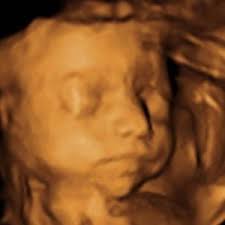

3d Ultraschall 31 Ssw Video Dailymotion